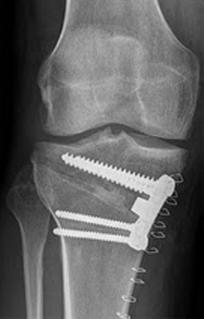

Bow legs, also known as genu varum, is a condition where the legs appear bowed outwards when standing. This condition can cause discomfort, pain, and even difficulty walking. In severe cases, surgery may be required to correct the alignment of the legs. In this article, we will discuss the causes, symptoms, and treatment options for bow legs, including the various surgical procedures available.

The treatment options for bow legs will depend on the severity of the condition and the underlying cause. Some common treatments include

The treatment options for knock knees will depend on the severity of the condition and the underlying cause. Some common treatments include